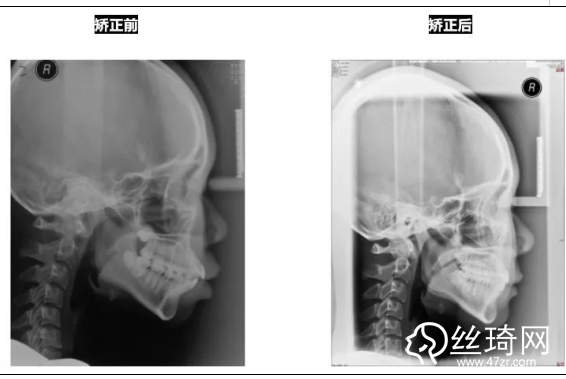

* 影像學(xué)檢查分析(以及調(diào)節(jié)前后影像對比):

頭顱側(cè)位片: